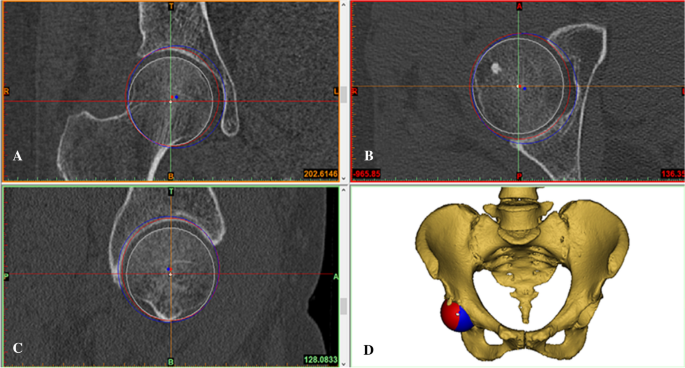

According to a study by Bonnin et al.6, the native hip rotation center is the femoral head center determined by the sphere fitting method. We used two spheres with different diameters to mimic the acetabular component implantation using two different methods: the conventional reaming technique and the anatomical technique (Fig. 1A–D). In the conventional reaming technique, the acetabular cup was in contact with the true floor of the acetabulum, but in the anatomical technique, the cup was positioned at the level of the subchondral bone. Then, the acetabular cup diameter with these two techniques was measured in the transverse plane. The medial and superior shifts of the rotation center were measured in the coronal plane in comparison with the native rotation center and verified in the axial and sagittal planes (Fig. 1A–C). Then, the pelvic position was standardized with reference to the anterior pelvic plane19,20,21 and the pubic tubercles (Fig. 2A). Thus, the coronal, axial, and sagittal images were reoriented according to the anterior pelvic plane and the line between the iliac spines. A plane passing through the center of the sphere was created to cut these spheres with different diameters to achieve a cup inclination of 45° and anteversion of 15° (Fig. 2B,C). The simulated acetabular replacement was performed by placing the component using two different reaming techniques. Component size was determined based on previous measurements of acetabular diameter. The component coverage ratio was then measured in the 3D environment. On the basis of the implantation simulation, an egg-shell cup with negligible thickness was developed to replace the implanted cup. Utilizing the simulation function of Mimics21,22, segmentations were performed according to the border between the covered and uncovered parts of the virtual cup (Fig. 3A,B). The coverage was calculated as the ratio of the covered area to the total surface area, which reflects the relative effective bone mass of the true acetabulum (Fig. 3C,D).

During the simulation of acetabular component implantation, the 3D, coronal, sagittal, and transverse views were presented simultaneously in Mimics software. Hip rotation center shift after application of the conventional reading technique and the anatomical technique in the coronal plane. The white point in the femoral head is the native hip rotation center; the blue point is the hip rotation center for conventional reaming technique; the red point is the hip rotation center for the anatomical technique. Medial shift and superior shift were determined by measuring the coronal and vertical distances from the blue and red points to the white point, respectively (A). (B–D). The axial plane (B), the sagittal plane (C), and the 3D model of the mimic implantation (D).